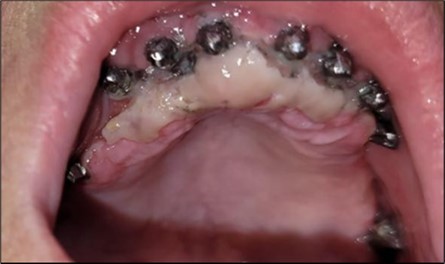

Considerations related to connective tissue grafting in post-extraction and post-implant defects – it is a technique that can be performed either by harvesting connective tissue from the tuberosity area, the palate, or the marginal palatal area, if the quantity is sufficient 11. It is done simultaneously with the rest of the bone regularization procedure; in this case, removal of the palatal gingival area was necessary anyway for easier cleaning and access to the frontal implants. On this occasion, after de-epithelialization, the tissue is used to restore the shape of the frontal gingival area after implant insertion (Figure 4, Figure 5).

Figure 4.Repair of the frontal area with connective tissue harvested from the marginal palatal area after extraction and crest regularization: (a) mucosal tissue piece harvested from the frontal palatal area before preparation; (b) prepared connective tissue piece placed between the frontal implants under the mobile mucosa.

Repair of the frontal area with connective tissue harvested from the marginal palatal area after extraction and crest regularization: (a) mucosal tissue piece harvested from the frontal palatal area before preparation; (b) prepared connective tissue piece placed between the frontal implants under the mobile mucosa.

Figure 5.Appearance of the mucosa from where the tissue was harvested and of the implants, 2 days after the corrective intervention.

Appearance of the mucosa from where the tissue was harvested and of the implants, 2 days after the corrective intervention.